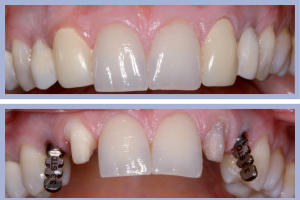

- Figg. 28a, b – Confronto tra inizio e fine trattamento

Nel presente caso clinico si tratta della sostituzione implanto-protesica di due incisivi laterali superiori agenesici in una Paziente di sesso femminile. L’agenesia degli incisivi laterali era associata a mesio-dislocazione dei canini al posto degli incisivi laterali e dunque l’obiettivo terapeutico era rappresentato dalla sostituzione dei denti mancanti in zona canina e dalla trasformazione protesica dei canini permanenti presenti in incisivi laterali.

La valutazione clinica al momento della consegna dei manufatti e clinico-radiologica a 3 mesi dalla consegna manifestava una completa integrazione tissutale con eccellente recupero estetico e funzionale (Figg. 29-30).